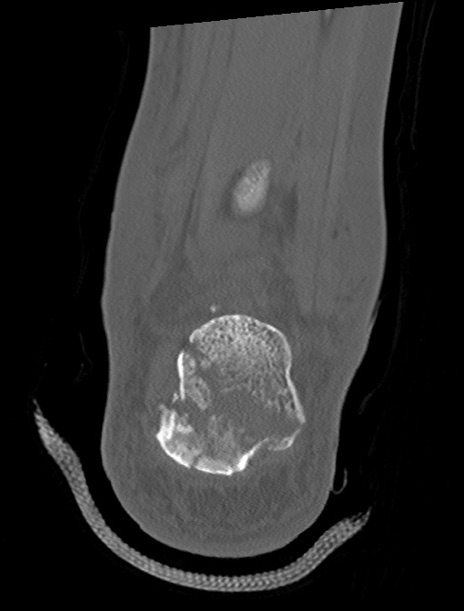

左足関節CT

矢状断像